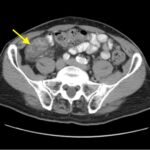

Small bowel diverticulitis is an uncommon subset of acute diverticulitis and can mimic many other intra-abdominal processes. As a result, imaging modalities such as ultrasound and computed tomography (CT) scan are especially important for timely recognition of diverticulitis and can expedite diagnosis and treatment and reduce complications. In the case described in this report, an 81-year-old male with history of esophageal cancer and recurrent diverticulitis with history of multiple bowel resections presented to the emergency department (ED) with right lower quadrant abdominal pain and constipation. Findings on ultrasound were suggestive of diverticulitis, and findings on CT of the abdomen and pelvis showed ileitis with phlegmon and micro-abscess suspicious for small bowel diverticulitis. ED providers should familiarize themselves with ultrasound findings of diverticulitis and be aware that diverticulitis can also present in the small bowel. Treatment of small bowel diverticulitis is similar to colonic diverticulitis.